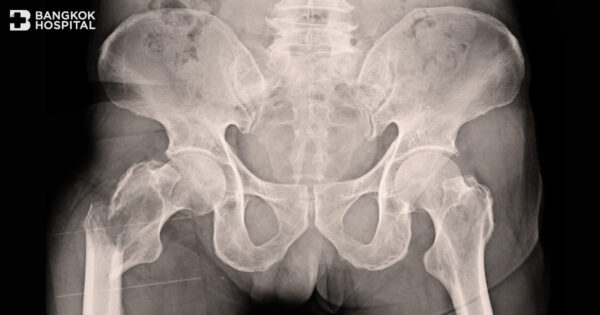

The Dangers Of Hip Fracture